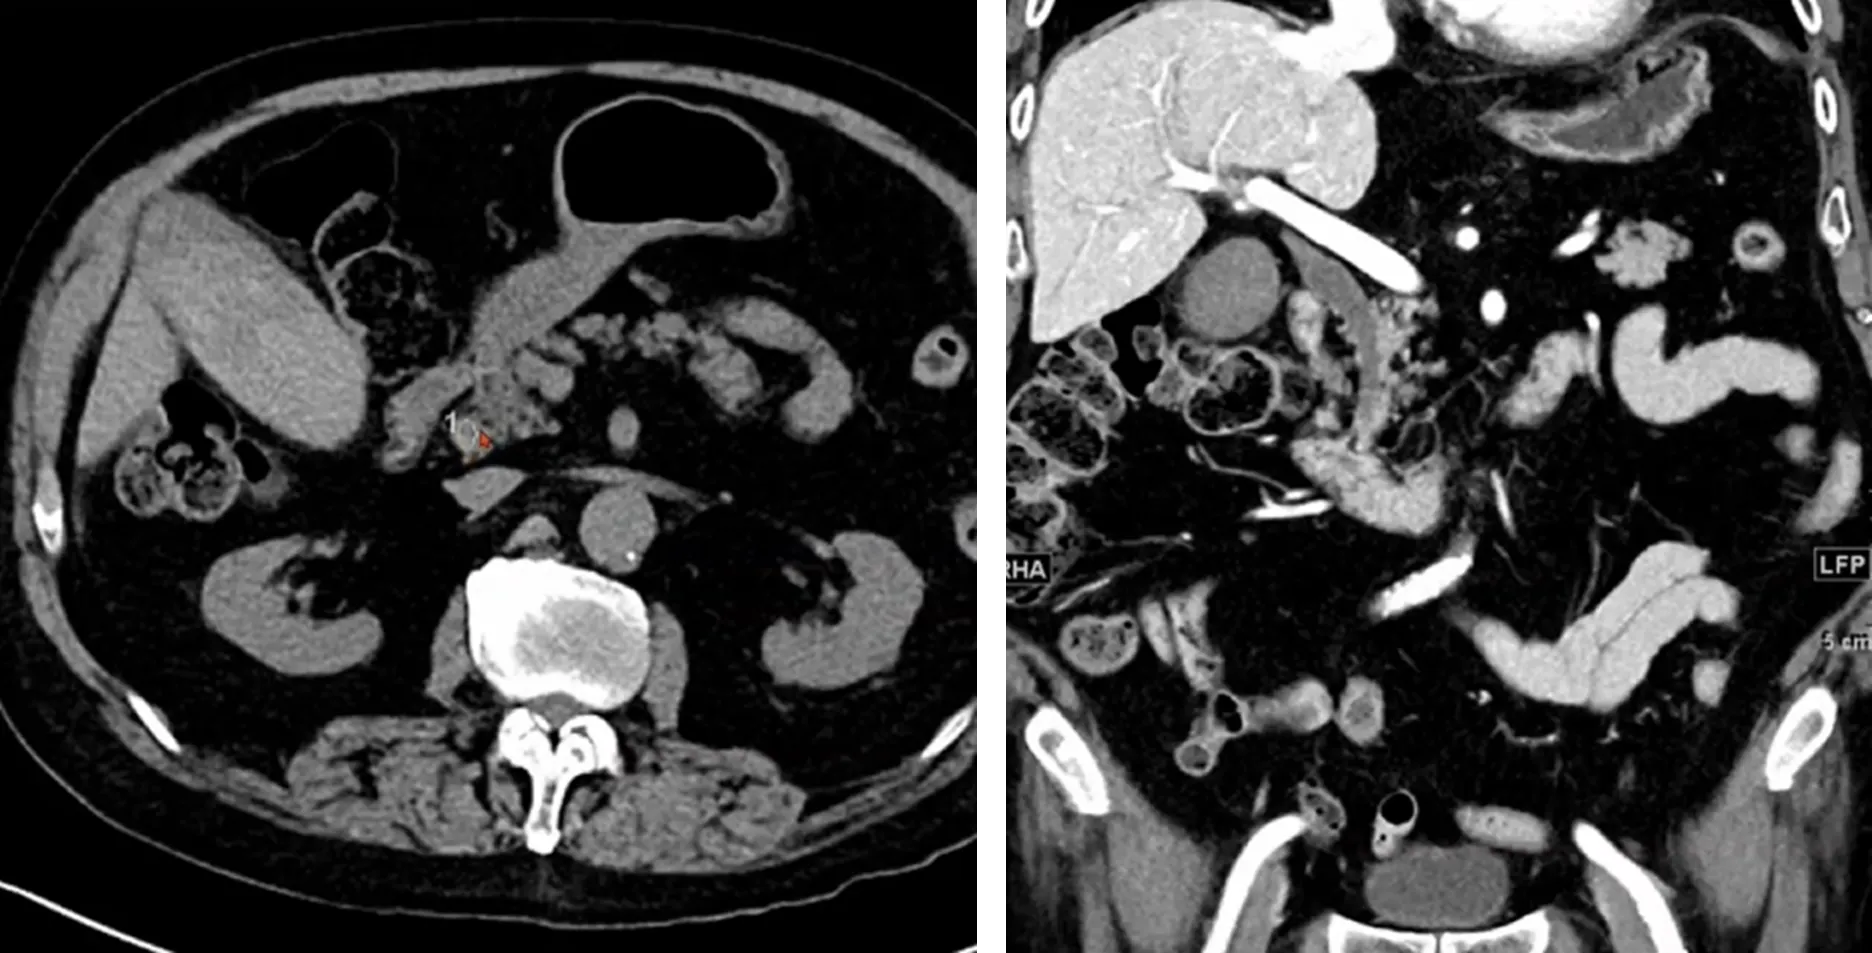

Case 8

•

F/51

C/C: LLQ abdominal pain for 7 days

Hx: HTN, DM, LC (alcohol, fatty change), ectopic pregnancy s/p Op

Refer from outside hospital due to surgery

Patient’s Symptom: RLQ pain 1week ago à migration of pain to LLQ two days ago

Hx of swallowing of fish bone (?) at 10 days ago

Temporary reading: One foreign body at posterior side of distal descending colon with localized peritonitis

Op finding

One toothpick at anterior wall of descending colon with penetration

Another toothpick at posterior wall of descending colon with penetration to retroperitoneum

Closure of micro-perforated descending colon

Toothpicks and cocktail sticks have the greatest propensity for migrating into any of the adjacent organs leading to fistulation and abscess formation

Toothpick can be difficult to perceive on CT, depending on the type of wood

Repeat non-contrast CT study will improve the diagnostic confidence

Multiplanar, three-dimensional reconstructions often be useful